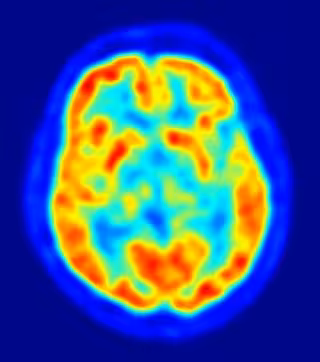

La mayoría de los genes asociados con enfermedades psiquiátricas se expresan antes del nacimiento en el cerebro humano en desarrollo, según un estudio publicado en 'Nature', encabezado por investigadores de la Universidad de Yale, en Estados Unidos. Además, los científicos han identificado cientos de diferencias genéticas entre hombres y mujeres, durante el proceso por el que sus cerebros toman forma dentro del útero.

La creación de cientos de miles de millones de células cerebrales, y el incalculable número de conexiones entre ellas, es una tarea tan compleja que el 86 por ciento de los 17.000 genes humanos estudiados participan en el proceso. El estudio evaluó no sólo qué genes están implicados en el desarrollo, sino dónde y cuándo se activan.

El estudio ha identificado los genes expresados ??en el cerebro humano -y cuándo y en qué parte del cerebro que se expresan- en 1.340 muestras de tejido de 57 sujetos de edades comprendidas entre los 40 días después de la concepción hasta los 82 años. El análisis proporciona un mapa sin precedentes de la actividad genética del cerebro en diferentes etapas de desarrollo.